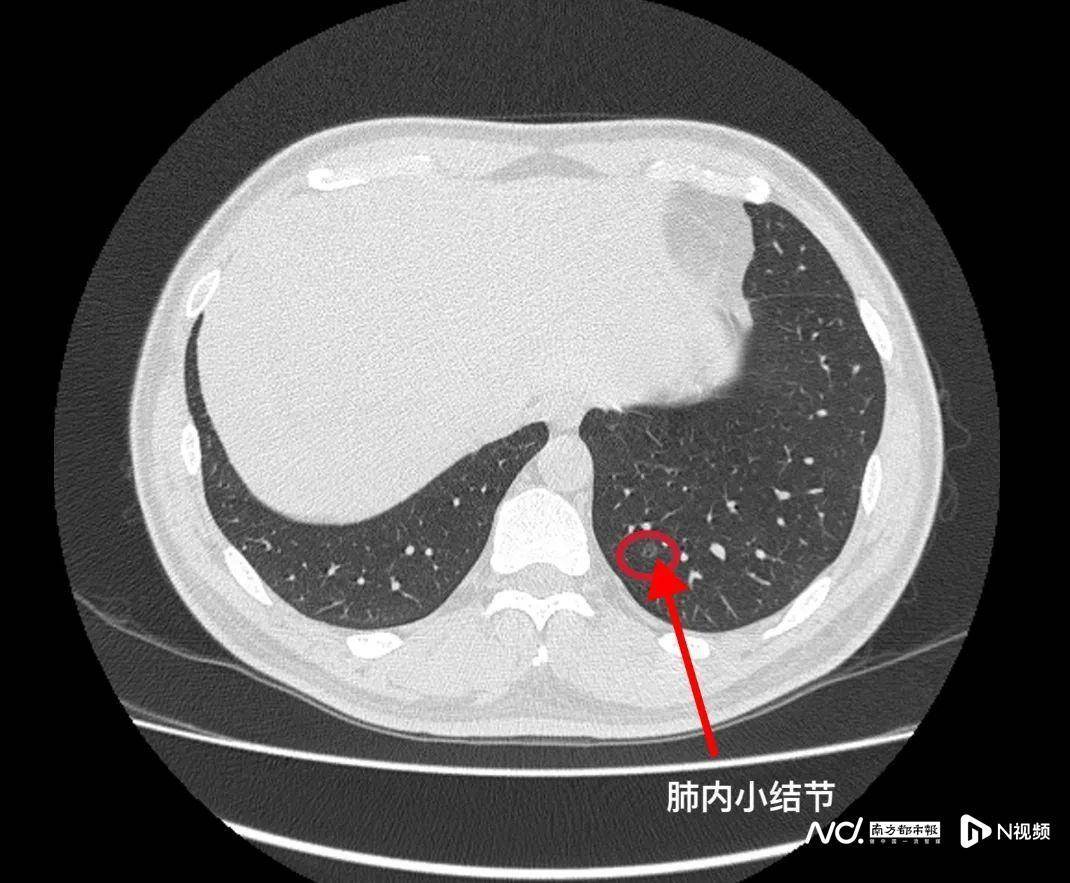

CT像“切西瓜”可分层看

CT又称电子计算机断层扫描,它是利用射线与探测器围绕人体的某一部位作一个接一个的断面扫描,像“切西瓜”一样,可以对“每一片”进行细致观察,还可以通过三维重建、血管造影等后处理技术,对一些复杂、细致病变的观察更具有优势,是X线检查的重要补充手段。